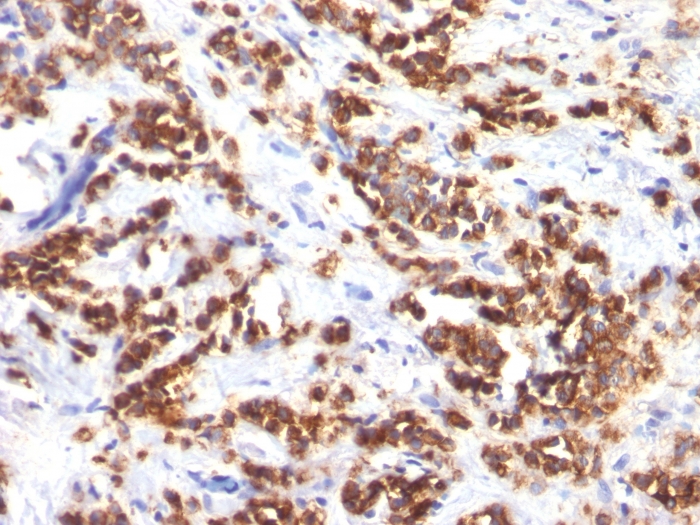

Formalin-fixed, paraffin-embedded human Lung Carcinoma stained with Milk Fat Globule Monoclonal Antibody (MFG-06)